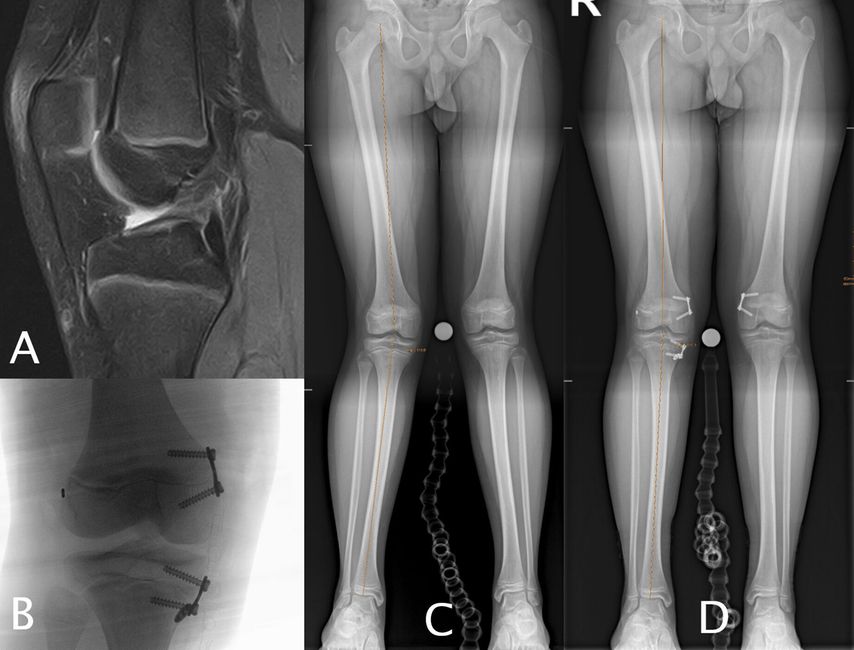

Abb. 1: 13-jähriger männlicher Fußballspieler mit VKB-Ruptur rechts (A), Valgusfehlstellung von 9° rechts aus dem distalen Femur (LDFA = 81°), proximaler Tibia (MPTA = 91°), Valgus von 5° Grad links primär aus dem distalen Femur (LDFA 84°) (C). Erfolgte Hemiepiphyseodese am medialen distalen Femur und an der medialen proximalen Tibia rechts sowie VKB-Plastik (4-Strang-Semitendinosus-Graft) (B). Korrekturerfolg vier Monate postoperativ (D)